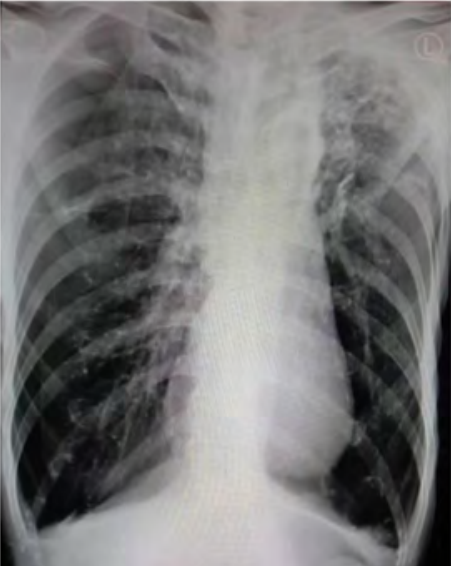

Satu jam setelah dilakukan dekompresi jarum, pasien merasakan sesak napasnya berkurang, pasien mulai merasa nyaman duduk bersandar dan retraksi berkurang. Pada pemeriksaan auskultasi, suara napas sisi paru-paru kanan mulai terdengar, meskipun masih lebih lemah dibanding suara napas di sisi paru-paru kiri. Tanda-tanda vital setelah dilakukan dekompresi jarum sebagai berikut: tekanan darah 108/75 mmHg, frekuensi nadi 110 kali per menit, frekuensi napas 30 kali per menit, dan saturasi oksigen 95-96% dengan oksigen non- rebreather mask 10 liter per menit. Hasil pemeriksaan radiologi foto polos toraks setelah dekompresi jarum adalah tampak penurunan volume pneumothorax pada hemitoraks sisi kanan, dengan ukuran sekitar 15%, dari sebelumnya 28%. Tampak pengurangan densitas bercak infiltrat pada lapangan paru-paru sisi kanan. Bercak infiltrat pada lapangan paru-paru sisi kiri tidak tampak perubahan. Efusi pleura bilateral relatif status quo ad anthem. Tidak tampak kelainan pada cor saat dilakukan pemeriksaan.

Gambar 2. Foto polos toraks setelah dekompresi jarum. Gambaran pneumothorax di sisi kanan telah berkurang dibanding sebelumnya.